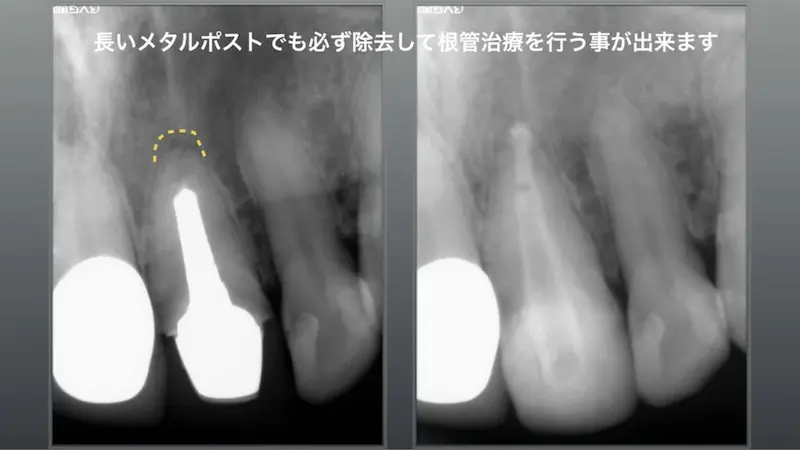

長いメタルポストで必ず除去して

根管治療を行うことができます

長くて太いメタルポスト(レントゲン上では白い部分)が確認でき、別な歯科医院では長いメタルポストは取れないと言われて来院、術前黄色の点線部分は大きく骨が吸収して、口腔内では時々腫れを繰り返す症状があるとのこと。

通常の根管治療を2回行い、数ヶ月後には骨再生がレントゲン上で現れ、外科をやらなくても通常の根管治療で虎ノ門吉松歯科医院では治す事が可能です。